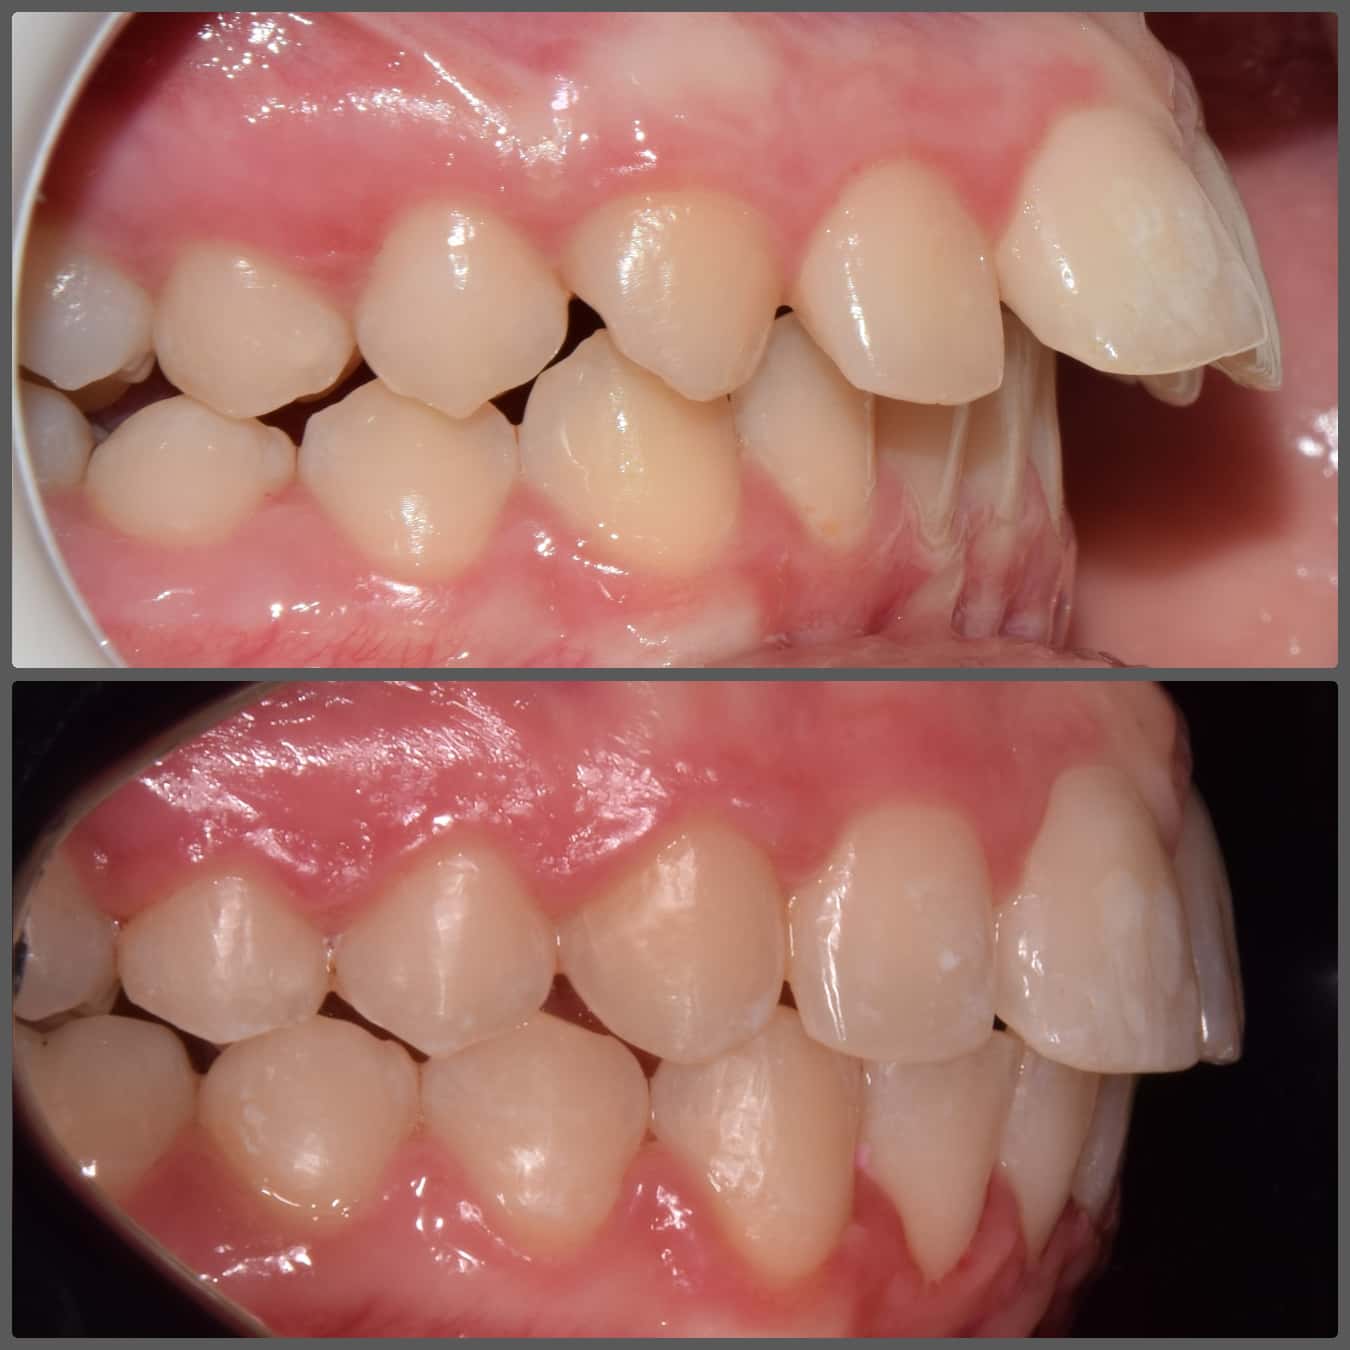

Bálint a 90 fokban elfordult jobb felső kismetszője miatt keresett meg engem. A vizsgálatokat követően kiderült, hogy a probléma ennél jóval komplexebb: súlyos keresztharapást, súlyos mélyharapást és felső rágósík billenést diagnosztizáltam nála. Alsó-felső H4 önligírozó fogszabályozó készülék, intermaxilláris gumihúzás és elülső harapásemelők segítségével korrigáltuk az eltéréseket. A bal oldali rágósík billenést fogszabályzási miniimplantátum alkalmazásával oldottuk meg. A bal felső-elülső fogakat felfelé mozgattuk, a miniimplantátumhoz húzva. Bálint esete igen komplex volt, ám kiváló együttműködésének köszönhetően 26 hónap alatt végeztünk a kezelésével (beleértve a 2-3 hónapos COVID-19 miatti leállást is). Az eredmény úgy gondolom magáért beszél!